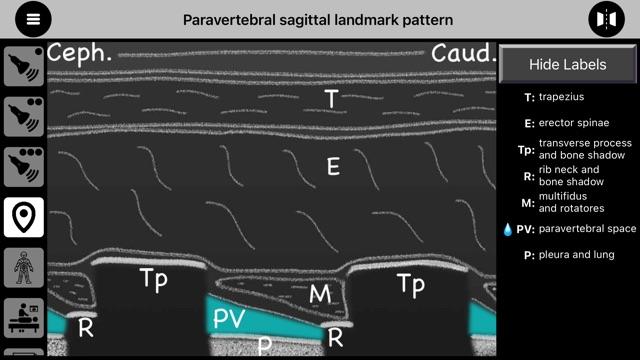

- 提供标志性草图,有助于开发标志性结构的模式识别,并供学员在考试中绘制,

- 地标图案草图,

- 提供标志性草图,有助于开发标志性结构的模式识别,并供学员在考试中绘制,

- 地标图案草图,